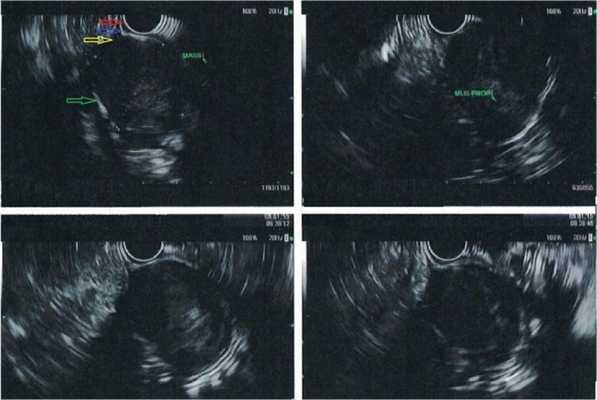

Эндосонография (ЭндоУЗИ, эндоскопическая ультрасонография)

Эндосонография — диагностическая методика , высокотехнологическое исследование, одновременно сочетающее в себе возможности эндоскопической и ультразвуковой диагностики.

Для исследования используют гибкий эндоскоп с видеокамерой и ультразвуковым датчиком. Его можно ввести в пищевод, желудок, двенадцатиперстную, прямую, толстую кишку, а также в дыхательные пути. Во время обычного ультразвукового исследования через кожу, когда нужно осмотреть орган, который находится глубоко, страдает четкость изображения. Эндосонография решает эту проблему. При помощи эндоскопа УЗ-датчик подводят максимально близко к исследуемому образованию. Во время исследования врач может провести тонкоигольную биопсию подозрительного образования. Использование в приборе очень высоких частот ультразвука (5,0; 7,5; 12 и 20 МГц) обеспечивает высокое качество изображения с разрешающей способностью менее 1 мм, недоступное другим методам исследования, таким как обычное ультразвуковое исследование, компьютерная и магнитно-резонансная томография, эндоскопическая холангиопанкреатикография. При этом эндосонография не сопряжена с риском рентгенологического облучения персонала и пациента, отсутствует опасность возникновения осложнений, свойственных ЭРХПГ.

Как проводится эндосонография?

Эндосонография верхних отделов желудочно-кишечного тракта напоминает гастроскопию, нижних отделов - сигмоскопию, колоноскопию. Процедура продолжается от 20 до 60 минут. Она занимает больше времени, когда ее дополняют тонкоигольной биопсией. Обычно эндосонографию проводят в состоянии медикаментозного сна - разновидность легкого наркоза. В этом состоянии пациент во время процедуры практически ничего не чувствует, может ощущать лишь небольшой дискомфорт. В ходе эндосонографии врач следит за артериальным давлением пациента, пульсом, уровнем кислорода в крови. Примерно через час врач разрешает встать, и, если состояние пациента в порядке, отпускает домой. В этот день нельзя садиться за руль и заниматься работой, требующей концентрации внимания.

Какое оборудование используется?

- радиального - перпендикулярны оси эндоскопа - сканируют 360 градусов - диагностический

- конвексного - параллельно оси эндоскопа - сканируют примерно 100 градусов - имеет специальный "инструментальный" канал

Эхоэндоскопы конвексного типа сканирования введены в клиническую практику с 1990-х годов и позволяют получать 100° секторное ультразвуковое изображение, параллельное оси эндоскопа. Использование аппаратов данного типа, оснащенных инструментальным каналом, позволяет проводить пункционную биопсию под ЭСГ-контролем (ЭСГ-ПБ). Комплектация эхосканеров допплеровским и соно-эластографическими блоками значительно расширяет диагностические и лечебные возможности исследования.